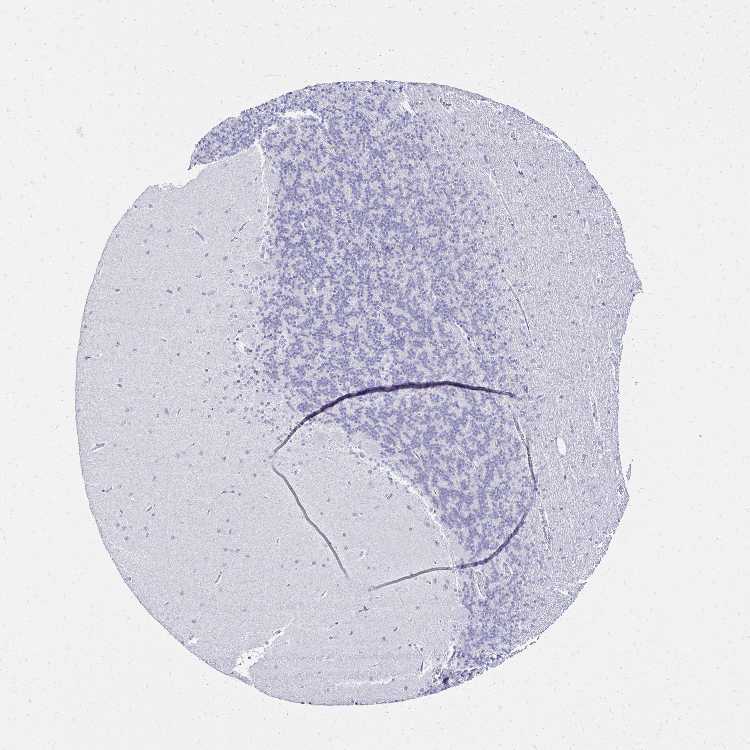

BRAIN CEREBELLUM Show tissue menu

CEREBELLUM - Expression summary

CEREBELLUM - Antibody stainingi

Antibody staining in the annotated cell types in the current human tissue is reported as not detected, low, medium, or high, based on conventional immunohistochemistry profiling in selected tissues. This score is based on the combination of the staining intensity and fraction of stained cells.

Each image is clickable and will lead to virtual microscopy that enables deeper exploration of all samples and also displays staining intensity scores, fraction scores and subcellular localization as well as patient and tissue information for each sample.

Antibody HPA035363Antibody HPA035364

Purkinje cells Not detectedNot detected

Cells in granular layer Not detectedNot detected

Cells in molecular layer Not detectedNot detected